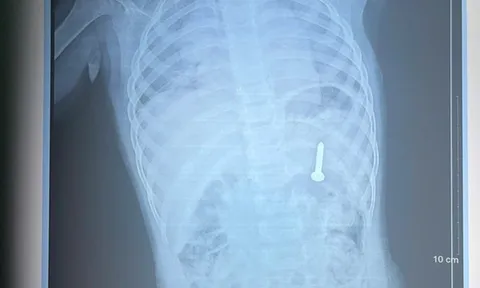

Người đàn ông đau bụng 36 tiếng, bác sĩ phát hiện "bí mật" bên trong

Các bác sĩ đã lấy ra chiếc chai nhựa mắc kẹt bên trong cơ thể một người đàn ông 38 tuổi sau một ca mổ phức tạp kéo dài hơn một giờ.